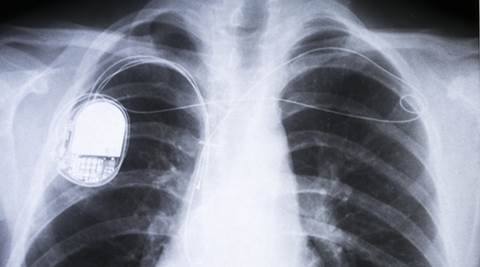

The technology may eliminate the medical risks, costs and inconvenience of having a battery replacement every five to 12 years for millions of people worldwide. (Source: Thinkstock Images)

The technology may eliminate the medical risks, costs and inconvenience of having a battery replacement every five to 12 years for millions of people worldwide, researchers said. About the size of a pocket watch, pacemakers are implanted under the skin through an incision in the chest. Wires, also called leads, connect the device to the heart and deliver electrical signals that regulate the heart’s activity. The new wireless option does not require leads because it rests inside the heart. This removes a potential point of failure, but the device still relies on a battery that must be replaced as often as the batteries that conventional pacemakers use.